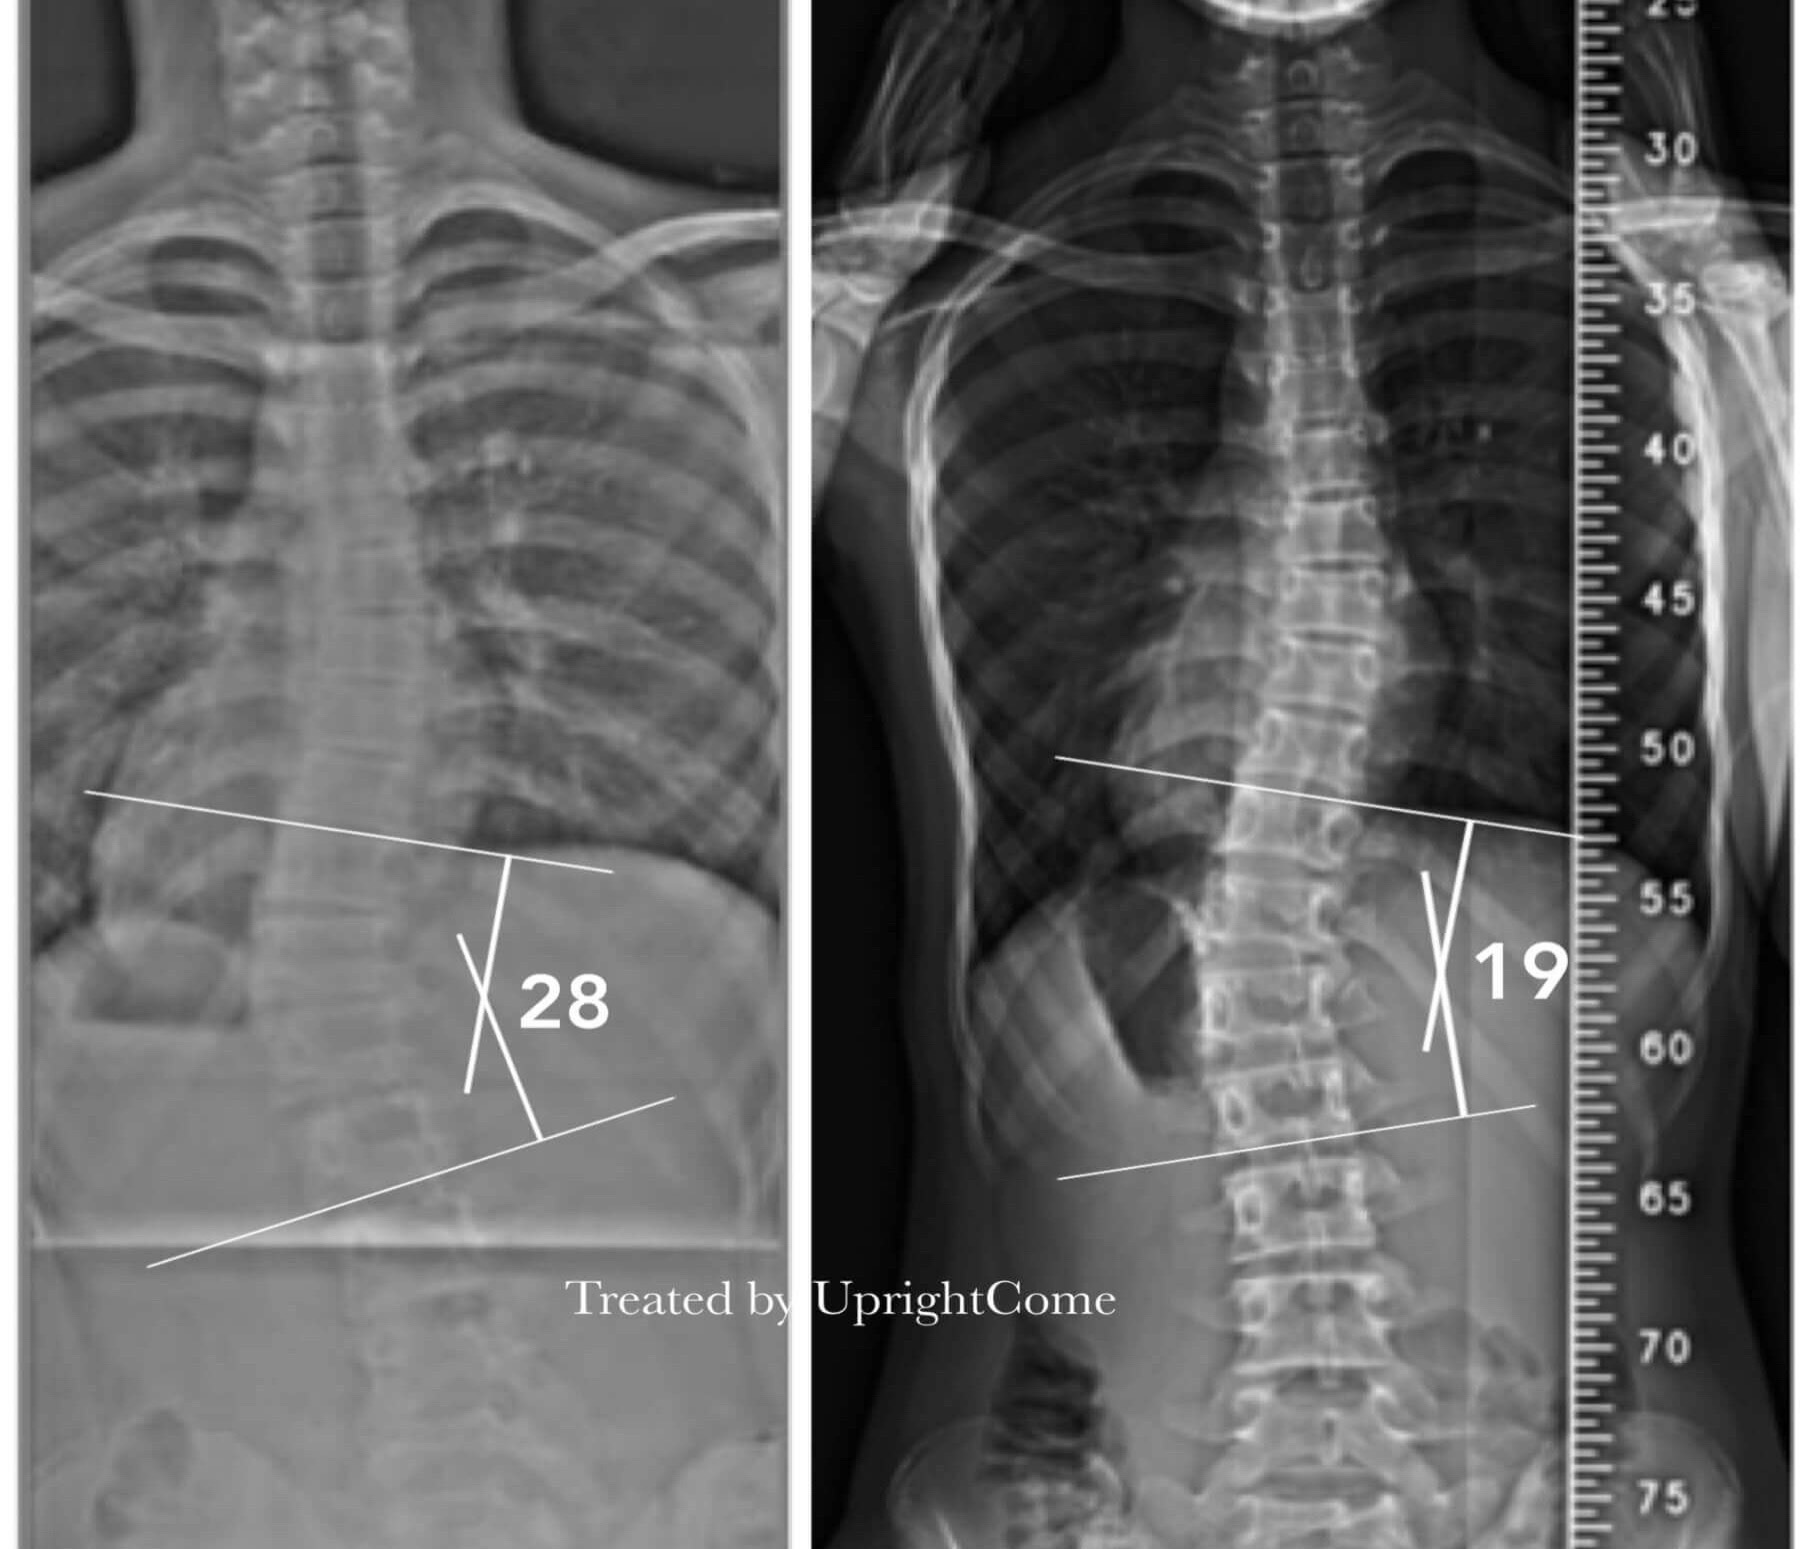

Case 13, 16 years old, 27° Cobb

![脊椎側彎患者經過側彎矯正治療後,腰椎側彎角度由27度減少到19度。]()